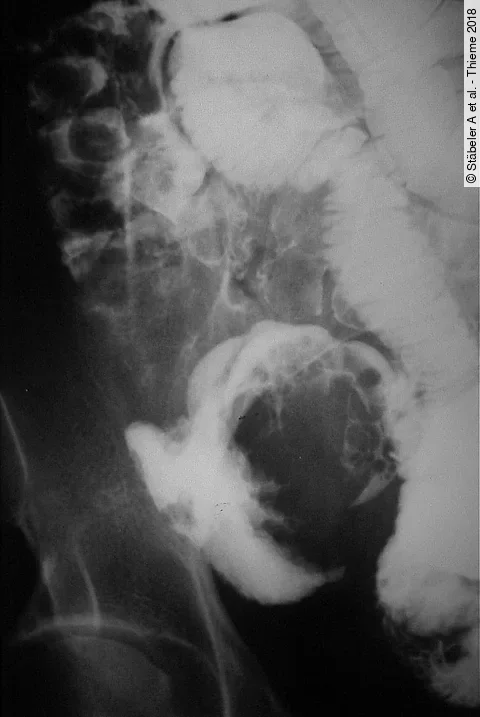

OriginaliaVergleich von 4 Methoden zur Behandlung der ektopen Schwangerschaft

Ziel dieser Studie war es, 4 Methoden zur Behandlung einer ektopen Schwangerschaft (ES) miteinander zu vergleichen: das aktive Beobachten und Warten, die Behandlung mit Methotrexat (MTX), entweder als einmalige Gabe oder in mehrfachen Dosen, und der operative Eingriff.